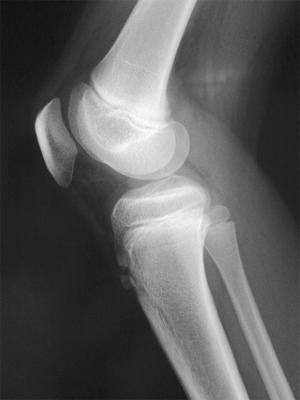

10歳の女児。1か月ほど前から運動後に膝の痛みを訴え、膝脛骨結節部に圧痛があった。単純エックス線写真を示す。運動後以外には膝の痛みの訴えはなかった。正しい対応はどれか。

jka6UPF5JytBzUX2dgxUT

1

ギプス固定

2

運動の制限

3

運動後の極超短波

4

運動後のホットパック

5

腸脛靭帯のストレッチ